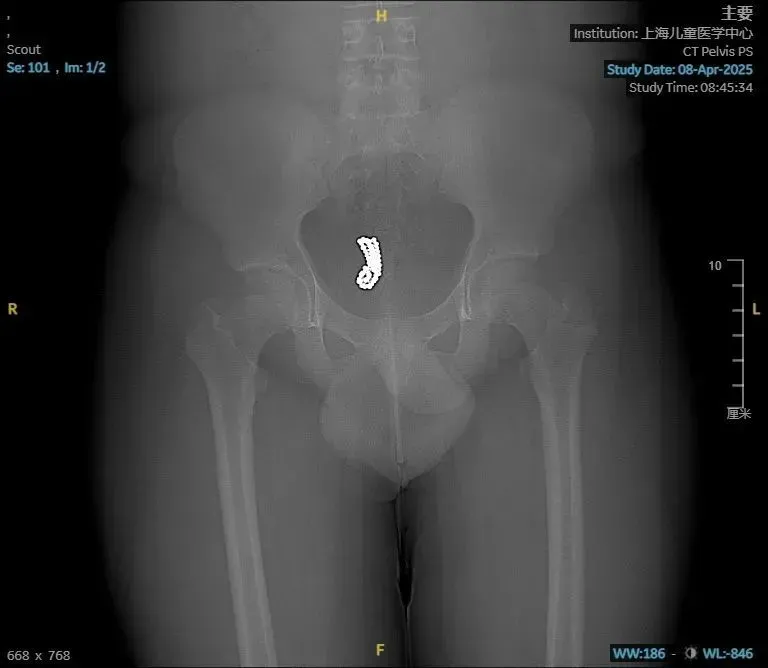

內地13歲少年性好奇 塞72顆磁力珠入膀胱致血尿(圖/翻攝新浪微博)

內地湖北省一名13歲少年,因連續3個月出現頻尿、血尿等症狀,到醫院求診,醫生赫然發現他的膀胱有大量異物。經手術取出,竟是一共72顆磁力珠。

醫生表示,小迪到醫院時已多次在當地接受消炎治療,但效果不佳,經過電腦斷層檢查,赫然發現膀胱內有大量異物,於是立即安排手術。醫生表示,「原本打算用膀胱鏡取出,但因磁力珠磁性強、彼此緊緊吸附,無法分開,只能開小切口進行手術,最終取出了72顆。」醫生透露,「手術室的人都不敢相信,還反覆數了3遍,確定是72顆。」